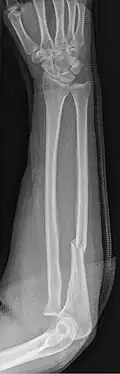

| Monteggia Fracture (type of ulna fracture) | |

- Monteggia fracture - a fracture of the near to elbow end of the ulna with the dislocation of the head of the radius at the elbow joint.[2]

Fractures of the ulna can occur at different levels of the bone: near the wrist, in the middle or near the elbow.[2] The fracture may be confined to the ulna or accompanied with damage to the radius or the wrist or elbow joints.[2]